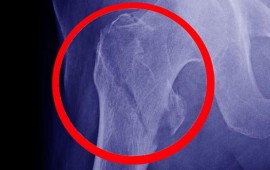

Atuamos em praticamente todas as áreas da Ortopedia e Traumatologia: ombro, cotovelo, joelho, quadril, mão, coluna e pé.